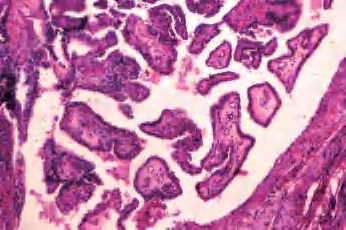

(1)滤泡亚型:由小至中等大小、不规则滤泡形成,实际上不含乳头结构,滤泡内含胶质,构成滤泡的上皮细胞有大而亮的核,含核沟和核内假包涵体。大约1/3此类肿瘤有包膜,预后与通常的乳头状癌相似(图3-44、图3-45)。

图3-44 甲状腺乳头状癌,滤泡亚型

图3-45 甲状腺乳头状癌,滤泡亚型